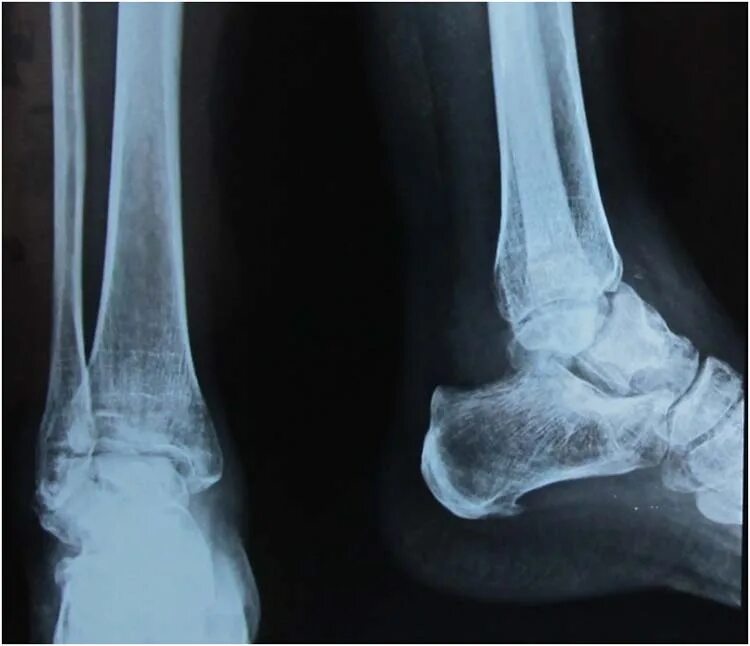

Артроз голеностопного сустава код